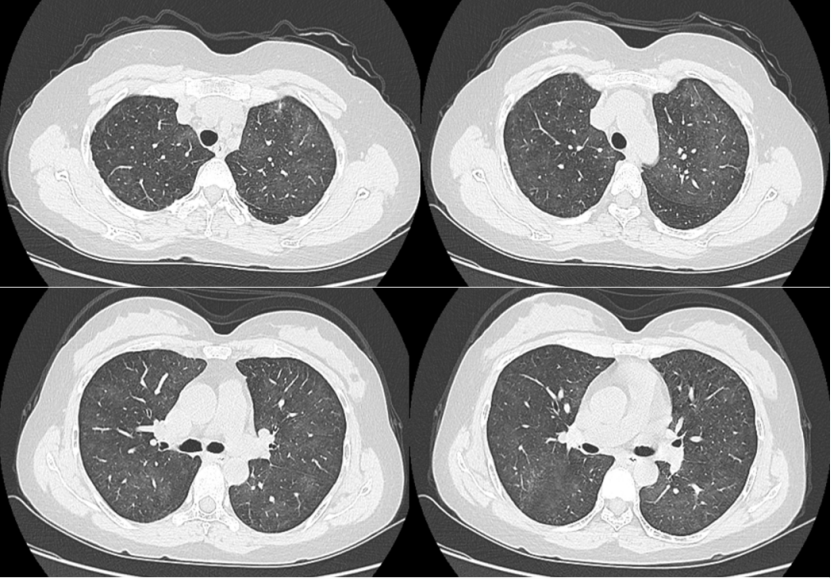

2)排异:肾移植术后2年,胸闷半月。双肺弥漫性渗出(图14)BALF分类计数:中性粒细胞占4.9%,嗜酸性粒细胞占17.1%,淋巴细胞占45.8%,组织细胞占20.1%,纤毛柱状上皮细胞占12%,未见肿瘤细胞及真菌感染依据。吉姆萨染色、PAS和PASM染色均阴性。患者BALF细胞计数以淋巴细胞及嗜酸性粒细胞为主,往往提示非感染性炎症,肾脏科会诊考虑为排异,予甲泼尼龙治疗后快速好转(图15)

图片

14  患者入院胸部CT

15  甲泼尼龙治疗前后胸部CT对比